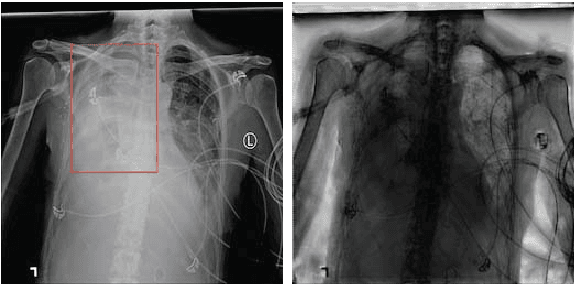

Chest X-ray examination plays an important role in lung disease detection. The more accuracy of this task, the more experienced radiologists are required. After ChestX-ray14 dataset containing over 100,000 frontal-view X-ray images of 14 diseases was released, several models were proposed with high accuracy. In this paper, we develop a work flow for lung disease diagnosis in chest X-ray images, which can improve the average AUROC of the state-of-the-art model from 0.8414 to 0.8445. We apply image preprocessing steps before feeding to the 14 diseases detection model. Our project includes three models: the first one is DenseNet-121 to predict whether a processed image has a better result, a convolutional auto-encoder model for bone shadow exclusion is the second one, and the last is the original CheXNet.